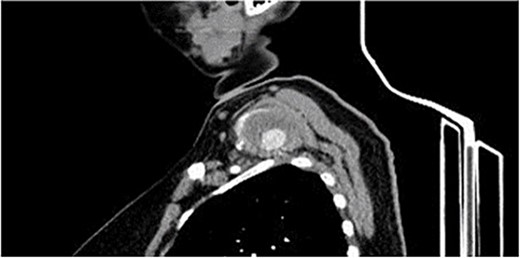

A 40-year-old female, who is a known case of type 1 diabetes mellitus, and hypothyroidism, on insulin and levothyroxine, was referred to our institute 4 months ago following trauma to her right shoulder from a falling drawer: complaining of swelling and pain around the right shoulder, palpable right distal pulses, and no discoloration or skin changes. Computed tomography angiography (CTA) showed partially thrombosed pseudoaneurysm at the right subclavian artery measuring 4.5 × 4 × 3.1 cm, most likely at the level of the costocervical trunk, specifically the highest intercostal artery (Figs 1 and 2). The subclavian artery and its branches were patent.

CTA, sagittal view showing the left supraclavicular pseudoaneurysm 4 × 3 cm.